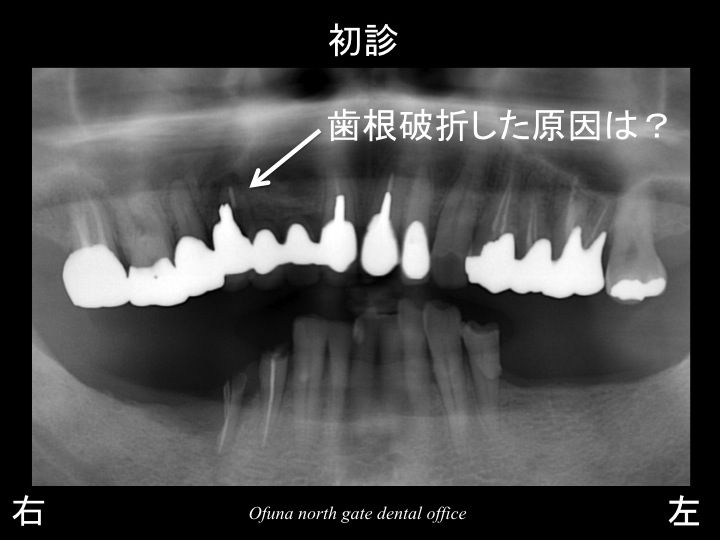

以下のレントゲンは、初診時になります。

下顎の左右の奥歯が欠損していました。

また、上顎右側前歯部 と 下顎右側が歯根破折 していました。

これらの歯は、神経がない歯です。

まず歯根破折 の一つ目の原因は、先程から解説しているように神経がないことです。

2つ目の原因は、ブリッジになっていることです。

ブリッジは、歯が欠損している部位を治療するために 欠損部位の両側の歯を削り、連結した被せ物を行う治療です。

そのため、ブリッジの土台となる歯には、どうしても噛む力の負担が加わりやすいのです。

そして ブリッジの土台となる歯が神経がない場合には、さらにリスクが高くなります。

3つ目の原因は、下顎の左右奥歯が欠損していたことです。

奥歯が欠損しているため、奥歯では噛めないことになります。

そのため、残っている前歯に負担が加わってしまったのです。

噛む力の負担が加わった前歯が

神経がない!

ブリッジになっている!

ということですから 当然のことながらダメ(歯根破折 )になる確立が高くなるのです。

上顎右側の歯が歯根破折 したことは、当然といえば当然の結果だったのです。